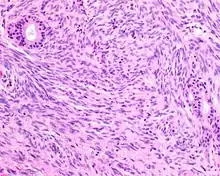

| A high-power view of a hematoxylin- and eosin-stained slide showing respiratory epithelial inclusions within a spindled cell neoplasm showing characteristics of a biphenotypic sinonasal sarcoma | |

- Infiltrative, highly cellular spindled cell neoplasm is poorly circumscribed and unencapsulated. Bone destruction or invasion is common. The cells show medium to long fascicles (nerve fibers), with a herringbone pattern. The cells are remarkably uniform with elongated nuclei. Delicate strands of intercellular collagen without ropy or dense deposition are seen. A very characteristic concurrent surface-type respiratory epithelial proliferation is found from the surface or in small cystic spaces around the cancer cells, often forming glands. The background may have a rich vascularity and usually has a small number of scattered lymphocytes. Extra growths or mitoses are rare, while necrosis, ulceration, and hemorrhage are usually absent.